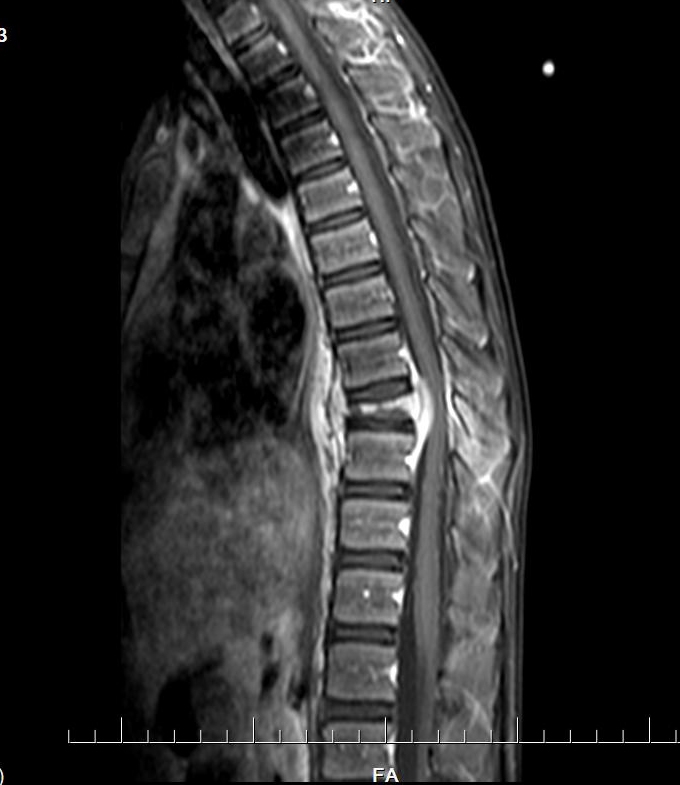

胸椎MRI平扫+增强扫描:第9胸椎椎体及其周围软组织感染性病变,并第9胸椎椎体病理性骨折。以结核性感染可能性大。

MRI

椎体脊柱病变可单发或多发,椎体可呈楔形或完全变扁呈钱币状,亦可呈溶骨性破坏,很少累及相邻的椎体椎间隙。CT及MRI可多层面显示椎体及附件的溶骨性破坏椎体的溶骨性破坏。常累及一侧椎弓根,同时还可清楚显示椎旁的软组织肿胀和包块,亦可显示椎管内受累的情况。